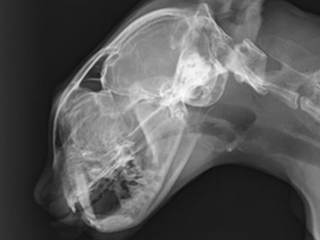

鼻がブーブー鳴るネコちゃん 4歳の男の子 小さい頃から鼻炎症状を繰り返す

レントゲン

左:鼻の奥が狭い(鼻咽頭狭窄)

右:バルーンで広げた後

バルーンで拡張後は長年悩まされていたお鼻の症状はほぼなくなりました。

繰り返すこともある疾患のため、現在経過観察を続けています。